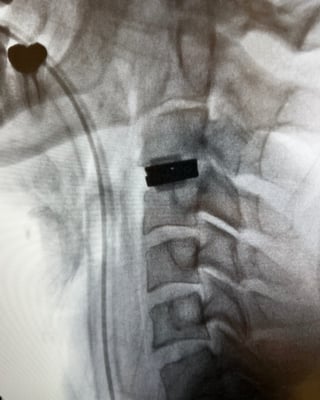

Post Op Image

Image: Post-operative x-ray of two Triadyme-C at spinal levels at C5-C6 and C6-C7 in the cervical spine.